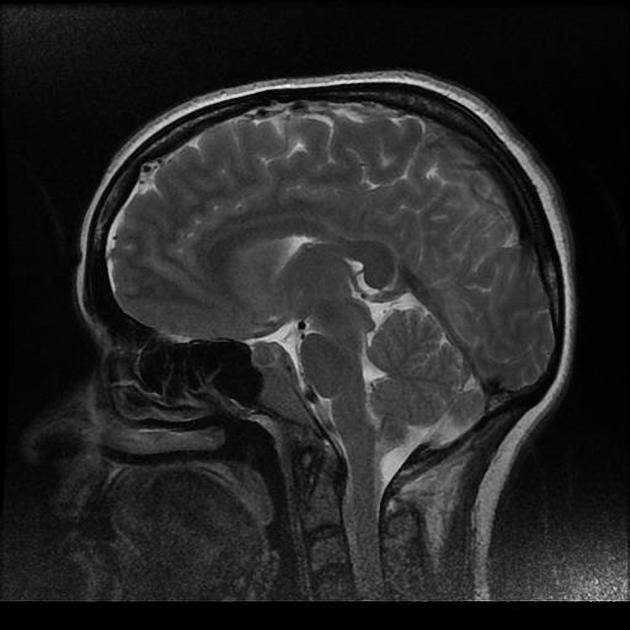

Marked obstructive hydrocephalus due to fourth ventricular outlet obstruction by fine septations

dandy walker malformation

This case illustrates a classic Dandy Walker malformation with associated aqueduct stenosis and obstructive hydrocephalus, a common associated feature

(although not part of the Dandy walker triad: